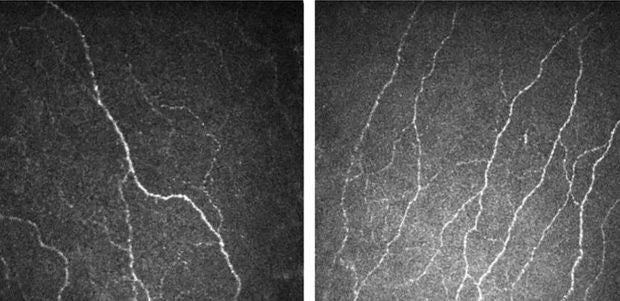

​A patient's corneal nerves that were damaged due to diabetes (left) became healthier and increased in number with Fenofibrate, a lipid-lowering drug. PHOTO: SINGAPORE NATIONAL EYE CENTRE

Dr Tan Hong Chang, a senior consultant at SGH’s department of endocrinology who was the co-author of the study, said: "For patients with diabetic corneal neuropathy, their corneal nerves are not healthy and tend to be fewer in number. The arrangement of the cells on the corneal surface is also disorganised.

"In this trial, we observed that fenofibrate was able to reverse these abnormalities, indicating that the nerves became healthier."